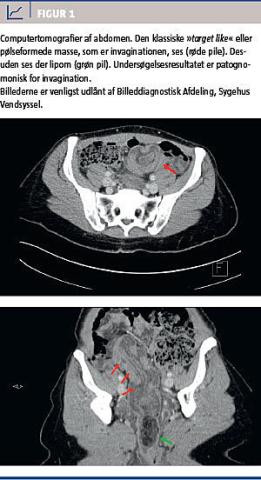

Objektivt fandtes patienten ikke akut påvirket. Hun var direkte øm og slipøm i venstre fossa og over symfysen. Der var ingen positive fund i øvrigt. Der var normale biokemiske værdier, fraset et C-reaktivt protein-niveau på 63 mg/l. En akut computertomografi (CT) af abdomen viste invagination i sigmoideum (Figur 1). Den strakte sig ned i øvre del af rectum til noget, der lignede reaktionsløst fedt. Slim-hinden i invaginationen havde dårlig opladning som tegn på kompromitteret perfusion. Derudover så man fri væske, men ingen fri luft.

CT af abdomen vil med høj sensitivitet (58-100%) være førstevalg af radiologisk undersøgelse [4]. De typiske fund er en målskive- eller pølseformet masse med lagdeling. Desuden kan der ses mesenteriske kar i lumen [2-4].